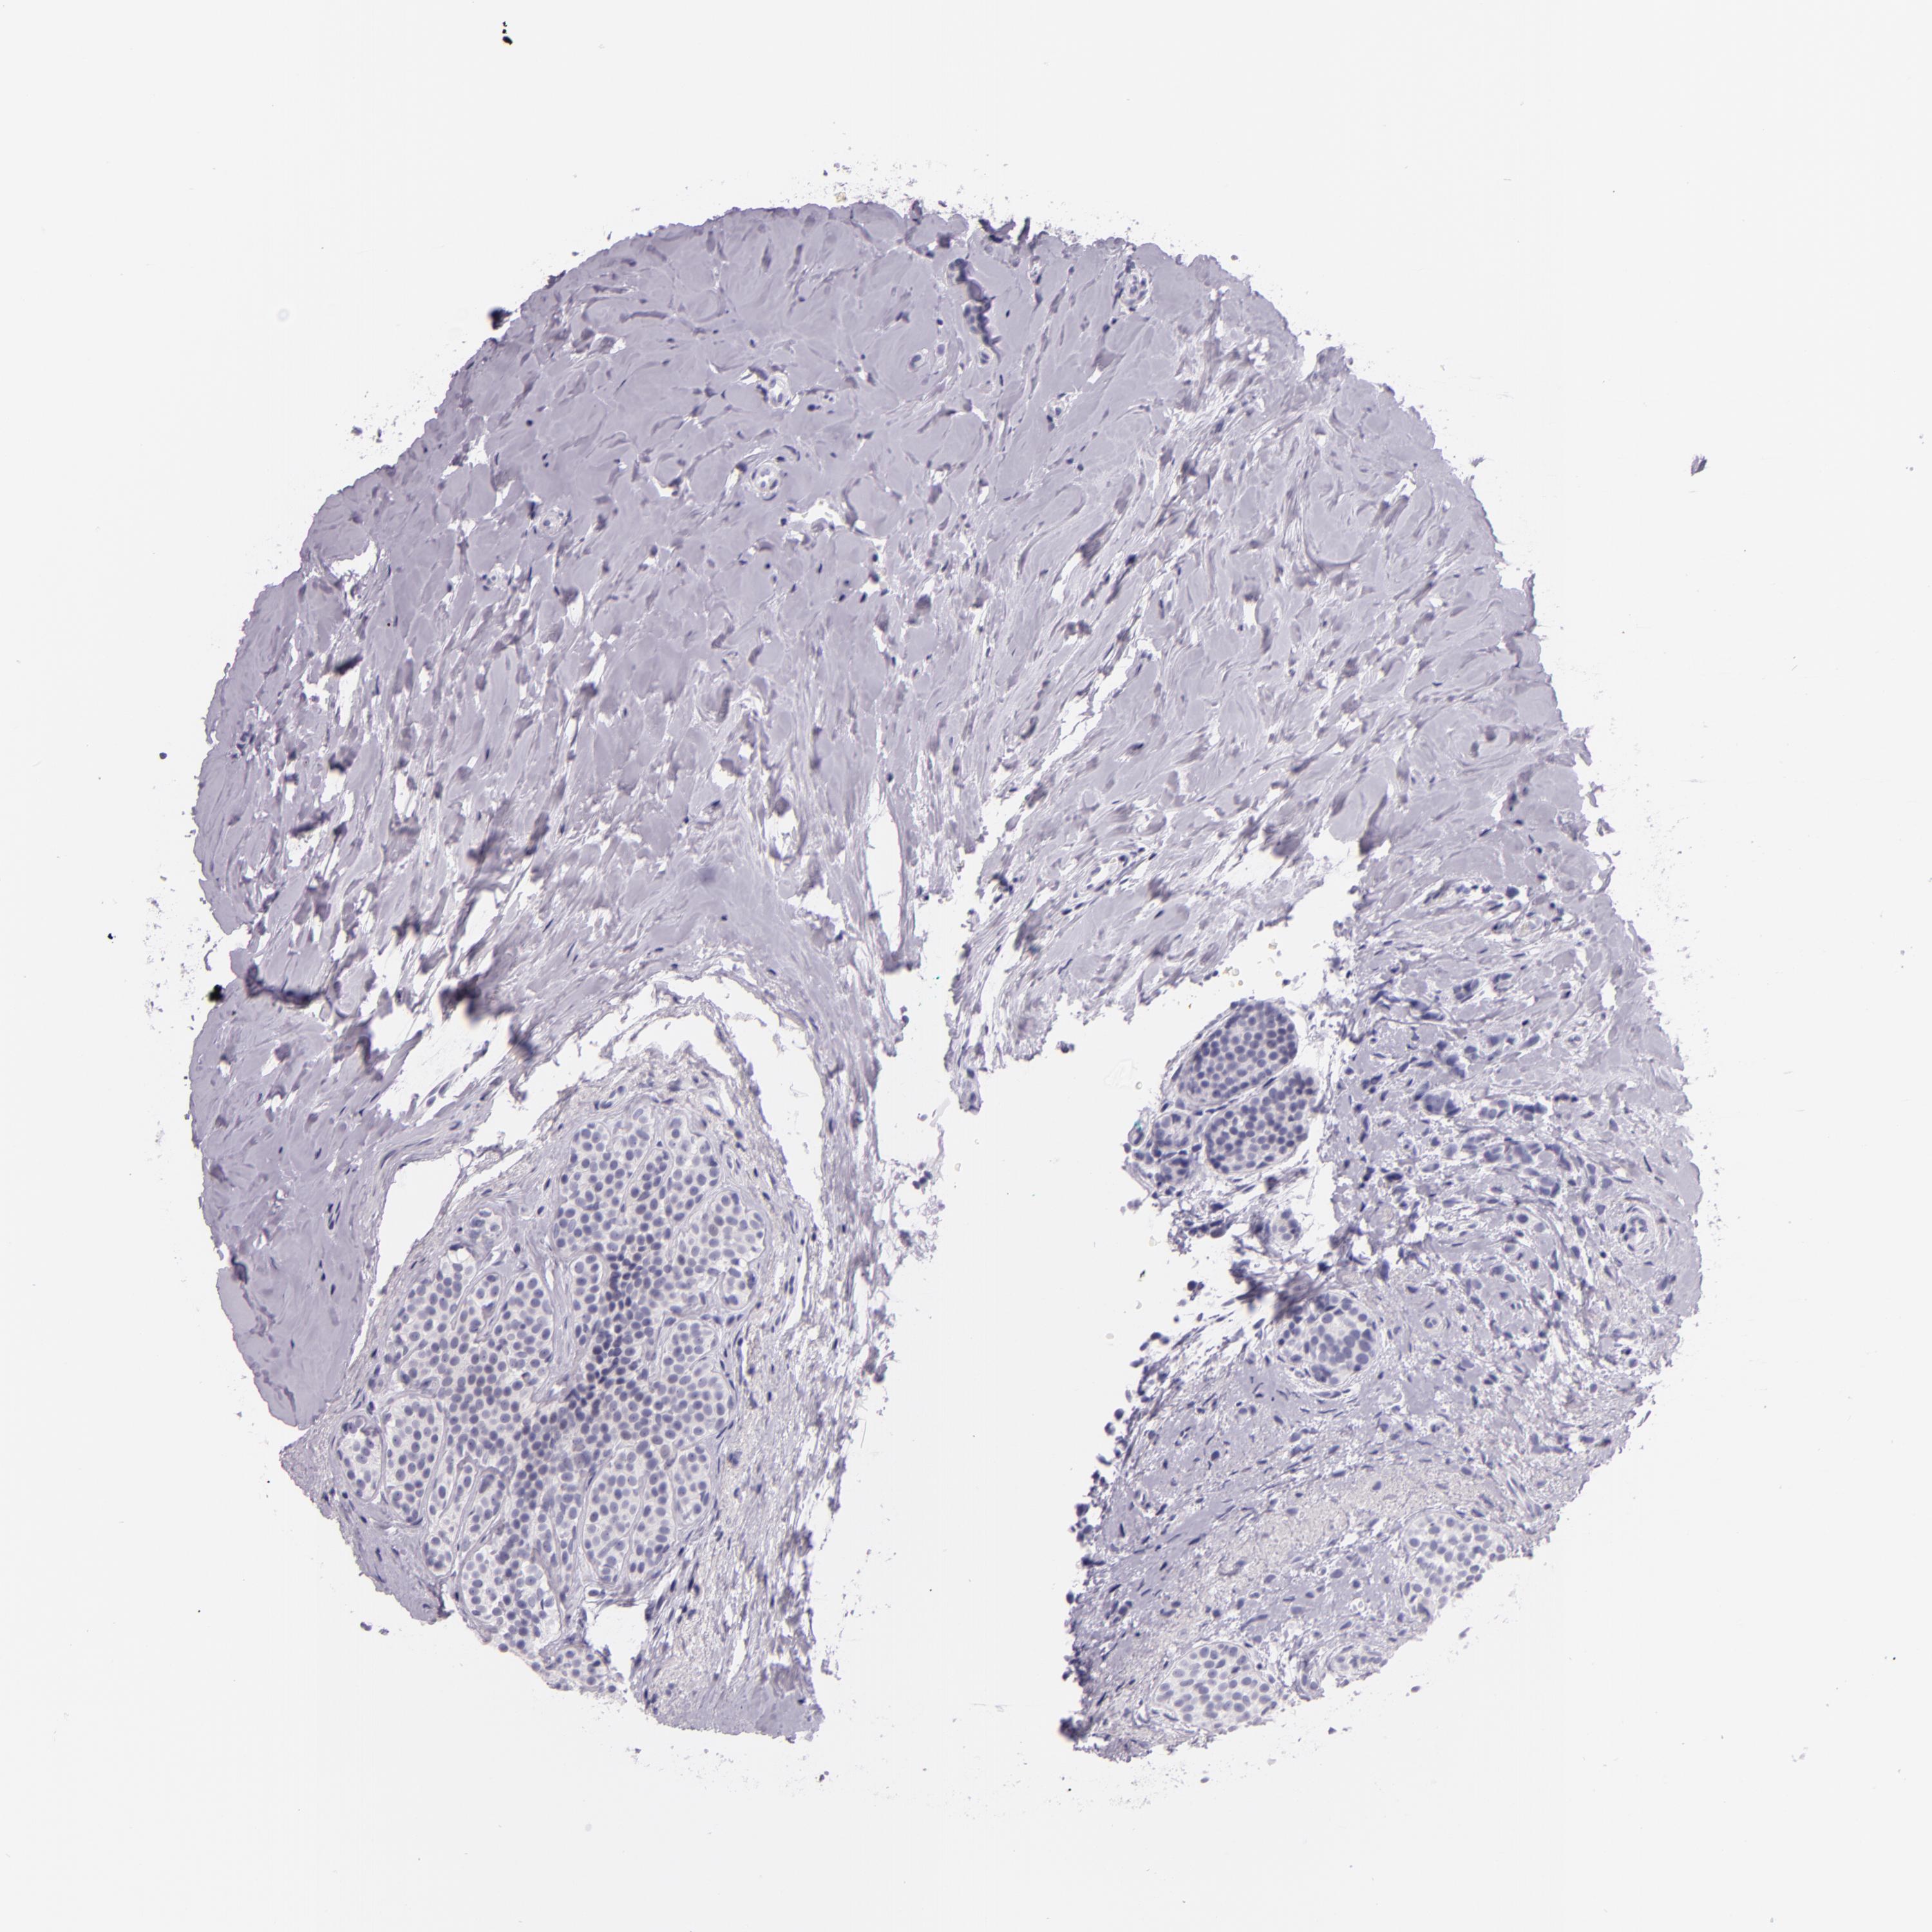

CANCER BREAST CANCER Show tissue menu

Breast cancer

Human cancer